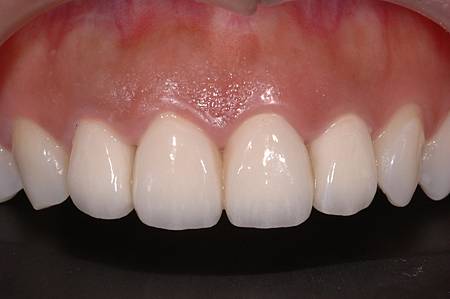

牙周病全口重建病例3

牙周病全口重建病例2

牙周病全口重建病例1